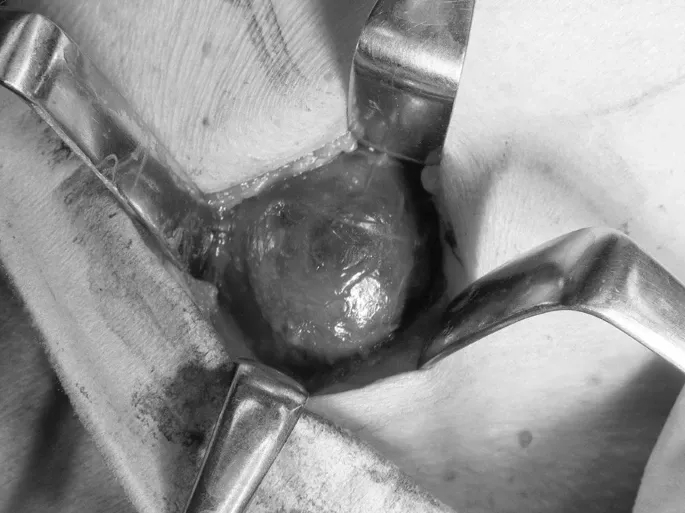

患者住院2天后在全身麻醉下行肿瘤切除术。肿瘤圆形,有包膜,呈深紫色,较容易与周围组织分离。由于肿瘤与颌下腺不相邻,行部分切除,术中行冷冻切片活检。肿瘤切除后释放大量黑棕色浆液。在肿瘤内部可见淡黄色颗粒状的乳头状结构向腔内突出(图2)。术中活检显示疑似甲状腺癌转移的细胞。基于此诊断,将肿瘤与周围组织分离并完整切除。同时切除肿瘤下侧2个12×8 mm和10×6 mm的淋巴结。肿瘤与周围组织无粘连,分离简单。用生理盐水冲洗创面,一期缝合完成手术。

图2. 术中发现